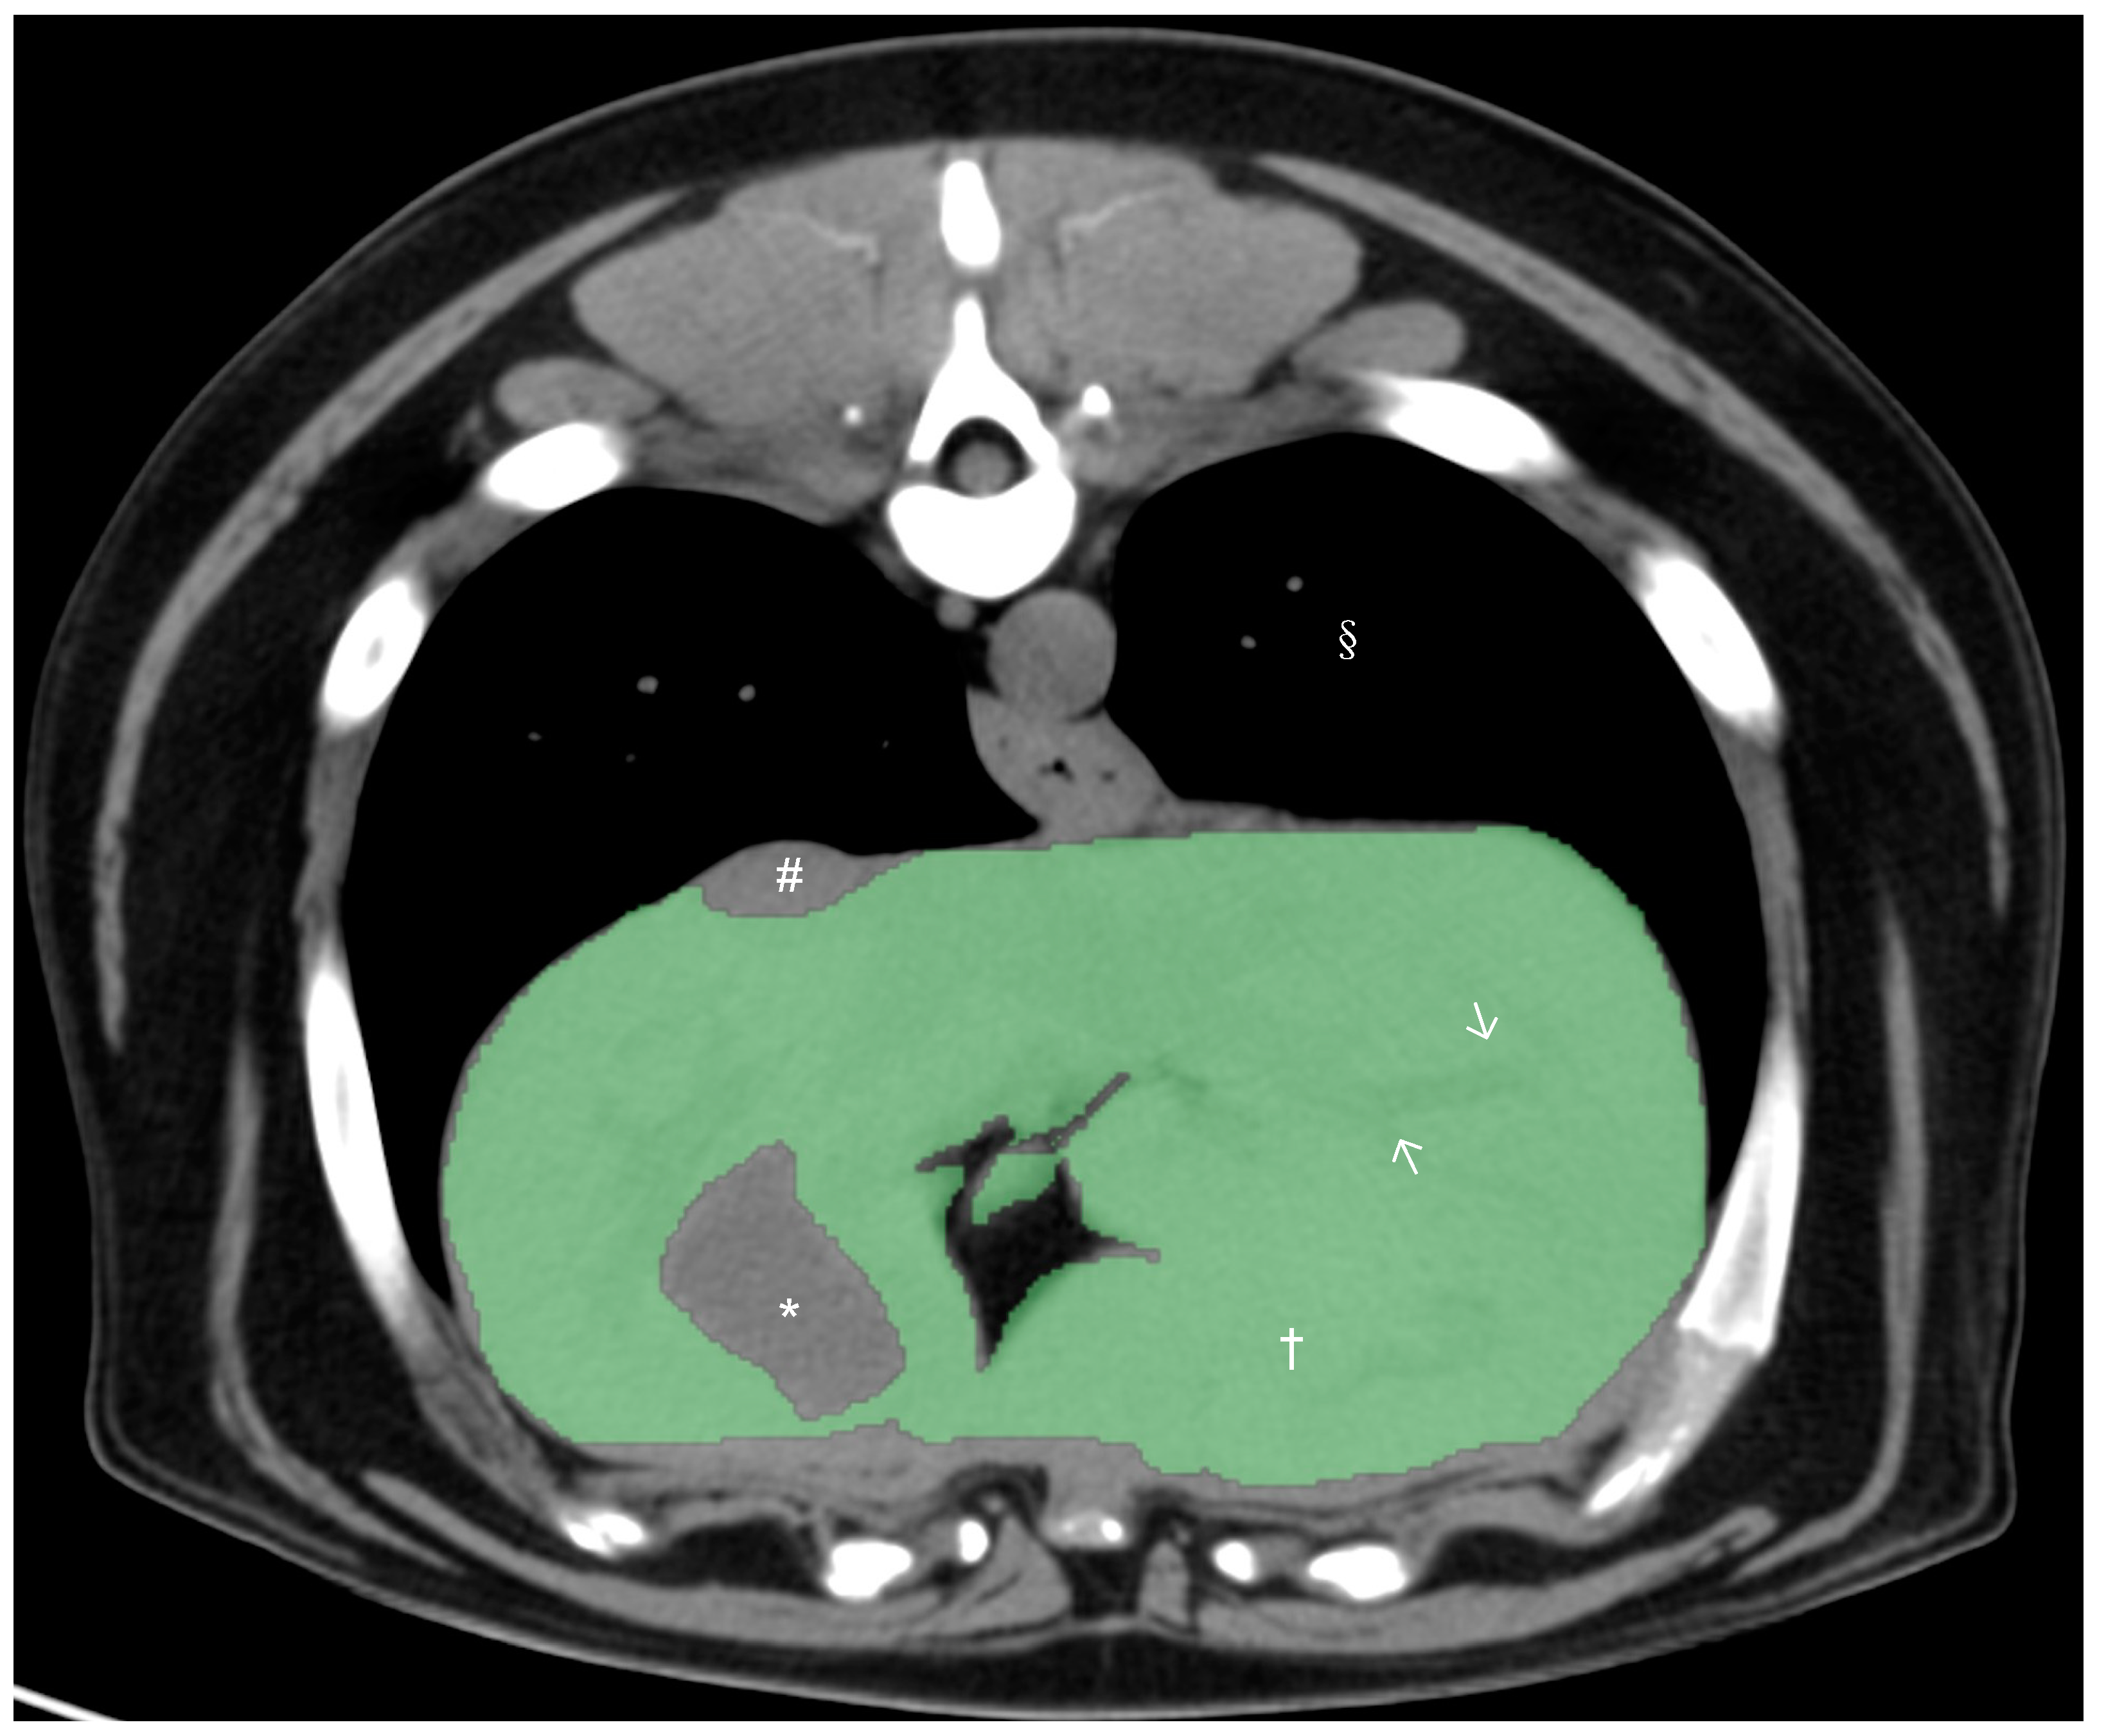

All CT studies were acquired with the dogs under general anesthesia or heavy sedation in sternal recumbency using the 64-slice third-generation CT units (Light Speed VCT, GE Medical Systems Inc., Waukesha, WI, USA) in helical scan mode. Pre- and post-contrast studies of the liver were reviewed by a board-certified radiologist (M.M.), and dogs with any hepatic abnormalities in the CT study were excluded from the present study. After exclusion, only pre-contrast studies were used for further CT hepatic volumetry. Manual CT hepatic volumetry was performed by a board-certified radiologist (M.M.) and two veterinarians (K.K. and H.M.) after training, supervised by a board-certified radiologist (M.M.), using a DICOM viewer (Horos 64-bit, Purview, Annapolis, MD, version 3.3.6.). The window width was set at 350 HU and the window level at 40 HU. Segmentation of the liver was performed by the manual drawing of the operator-defined region of interest (ROI) on pre-contrast transverse images of the entire liver from the cranial margin of the liver at the diaphragm to the most caudal margins of the liver. The hepatic vessels within liver parenchyma were included within the ROIs, and the gallbladder and visible hepatic lobe fissures and vessels present outside of the hepatic parenchymal margination (including caudal vena cava) were excluded (Figure 1). After manual drawing of ROIs on hepatic parenchyma in all transverse images, hepatic volume was calculated using the following formula: Σ{each slice area (cm2) × slice thickness (cm)}.

Figure 1. Precontrast transverse abdominal CT images used for measuring liver volume in dogs. The segmentation of the liver was manually selected as Region of Interests (ROIs: green regions). Note that the hepatic vessels within liver parenchyma were included (white arrows). The gall bladder, hepatic lobe fissure, and hepatic vessels present outside hepatic parenchyma were excluded. Window width, 350 HU, and window level, 40 HU. Liver parenchyma (†), gallbladder (*), caudal vena cava (#), and pulmonary parenchyma (§).